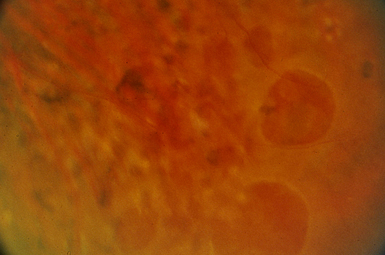

Macular Degeneration

There are two types of Macular Degeneration – Wet and Dry. If it becomes Wet, early intervention can usually preserve sight.